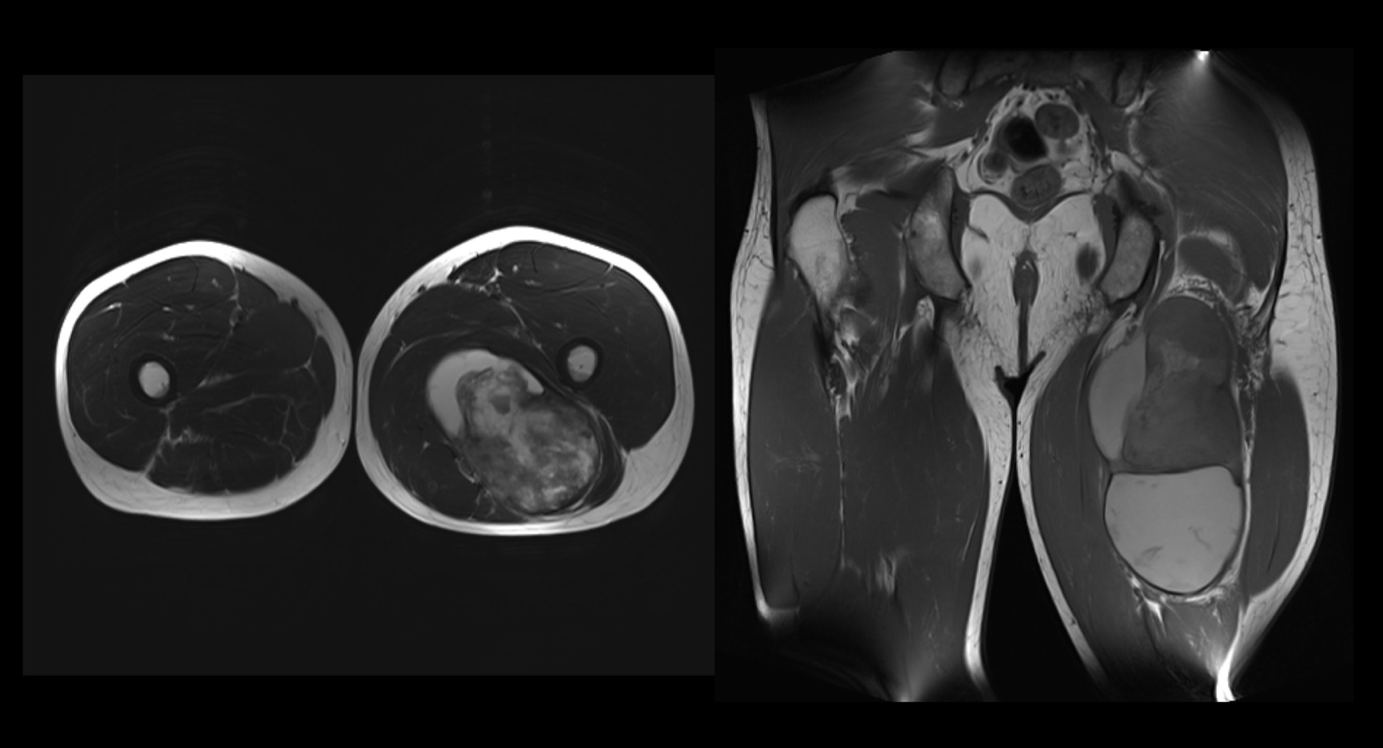

Non è raro che si verifichi un gonfiore muscolare nella parte superiore o inferiore della gamba a causa di una trombosi venosa profonda (TVP). Queste vengono sempre escluse per prime. Se la TVP non è confermata, è necessario ordinare una diagnostica per immagini per escludere altre cause. Nel caso del signor K., la risonanza magnetica ha mostrato una massa che aveva origine nel muscolo della coscia sinistra, che si è rivelata essere un sarcoma. I sarcomi sono tumori maligni e altamente aggressivi di origine mesenchimale. I sarcomi sono molto più rari dei carcinomi. Costituiscono circa l'1% delle neoplasie maligne, ma possono metastatizzare e avere un decorso letale. La terapia primaria in questo caso sarebbe la resezione totale. Se il femore è colpito, si dovrà prendere in considerazione l'amputazione dell'arto.

image3.png

Figura 5: Immagini RM assiali e coronali delle cosce su entrambi i lati. Questa mostra una massa eterogenea, cistica e in parte solida, che origina dal muscolo bicipite femorale caput brevis a sinistra.